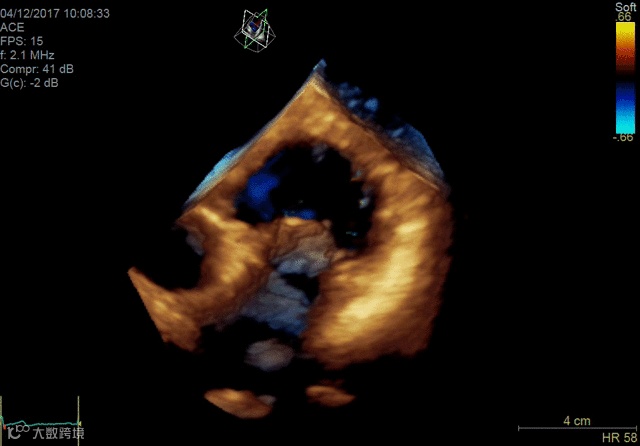

较慢的帧率和3-D超声的较大费用限制了其广泛采用,但其在一些专业领域的应用有助于快速扩展治疗,如经导管结构性心脏介入。当专家使用成像进行程序规划或指导时,3-D的使用具有很大的应用,其中3-D可以提供解剖学的“外科医生视野”。该技术还用于帮助指导复杂解剖结构中的导管手术。

Vivid E95心脏成像系统

2018年,GE医疗集团发布了其cSound图像重建技术的Imaging Elevated版本。该技术有助于Vivid E95心脏成像系统的成像质量,工作流程和量化。它利用GPU处理来提高音量帧速率,GE称为音量最大值或Vmax。与上一代系统相比,这使得TEE的帧速率几乎可以达到三倍。

佳能Aplio 900 CV系统还在2018年推出了一种新方法,通过称为四腔室跟踪的回声可视化心脏。它在一个三维视图中跟踪所有四个腔室的血容量。它提供腔室的舒张末期和收缩末期视图。这允许一次完成整个心脏功能的图像,而不是一次查看一个腔室。